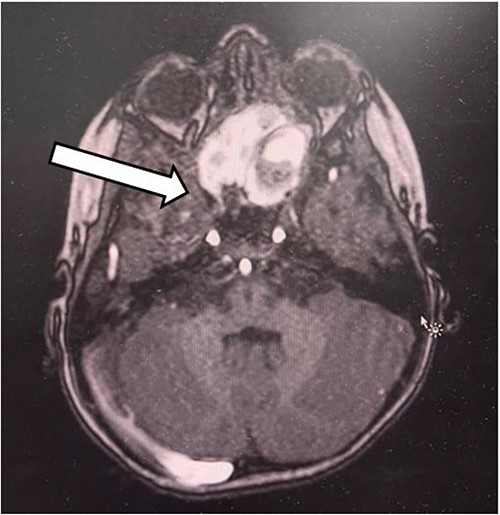

The patient had undergone computed tomography of the paranasal sinuses (CT PNS) and magnetic resonance imaging (MRI) brain with contrast. The MRI showed a heterogeneous mass predominantly occupying the left nasal cavity, left maxillary, and sphenoid sinus, destructing the osseous structure, as well as extending to the medial aspect of the left orbital wall causing minimal proptosis (Figs 1 and 2). Magnetic resonance angiography showed no prominent feeding vessel of the mass. CT PNS demonstrated a heterogenous soft tissue nasal mass extending into the sphenoid wing through the sphenoid sinus, causing skull base erosion but no intracranial invasion.